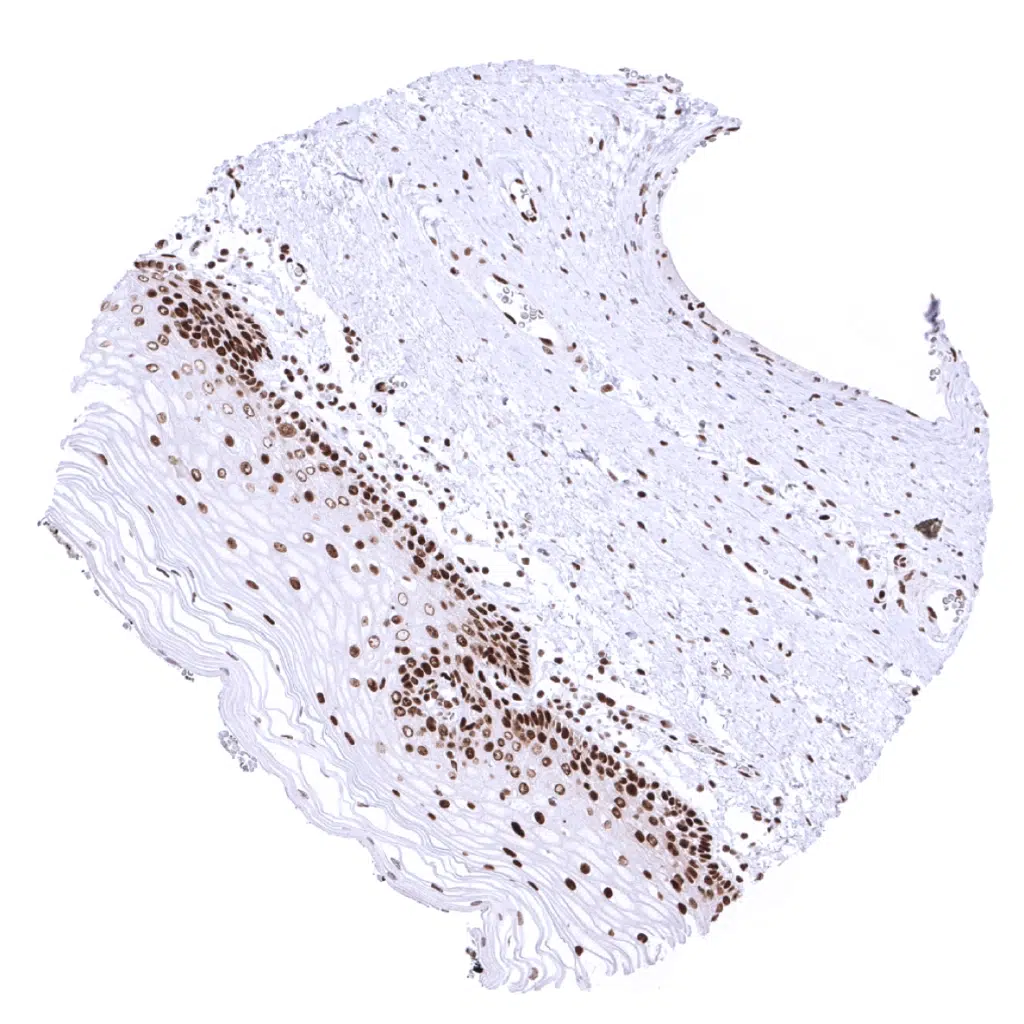

Colon, mucosa – In the colon epithelium, the MSH2 staining intensity decreases from the bottom to the top of the crypts.